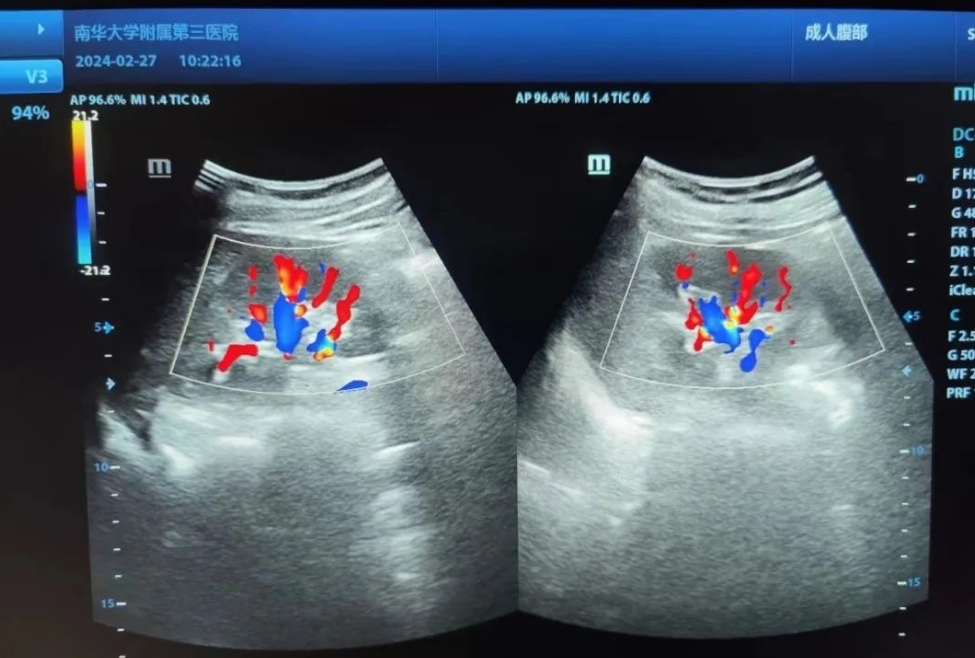

3、医生,这个红色和蓝色的是什么啊?

这个代表的是血流。也并不是大家认为的红色代表动脉,蓝色代表静脉;而是红色代表朝向探头的血流,蓝色代表背离探头的血流。颜色是用来区分血流方向,而不是区分动静脉血流。